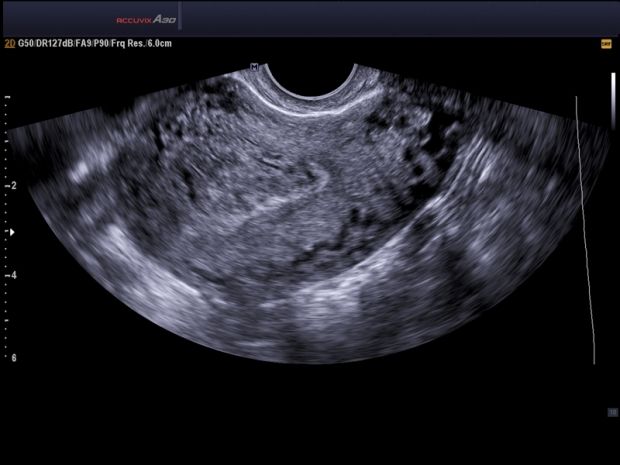

Міоми матки відрізняються великою різноманітністю клінічного перебігу. У деяких хворих захворювання носить важкий характер, призводячи навіть до астенізації і невротизації. Скарги хворих залежать від багатьох факторів: локалізації і величини пухлини, вторинних змін в міоматозних вузлах, тривалості захворювання, наявності супутніх змін в статевих органах тощо. Переважання тих чи інших факторів відображається на симптоматиці захворювання.